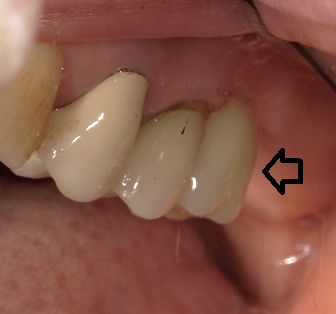

手術後半年の写真です。